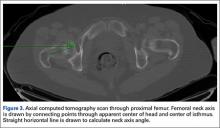

As we made all measurements for each femur off a single CT scan, we were able to use a straight horizontal line—drawn on-screen with a software tool—as a reference for measuring rotation. On a distal femur cut, the PC axis is drawn by connecting the posterior-most points of both condyles. The software calculates the angle formed—the PC angle (Figure 1). This angle, the degree to which the PC axis deviates from a straight horizontal line on-screen, can be used to account for gross rotation of the limb on comparison of images. The AP axis of the femur is the axis perpendicular to the PC axis. As such, the PC angle can also be used to determine degree of deviation of the AP axis from a straight vertical line on-screen. The AP axis was used when calculating the LA axis at the various levels of the femur (Figure 2).